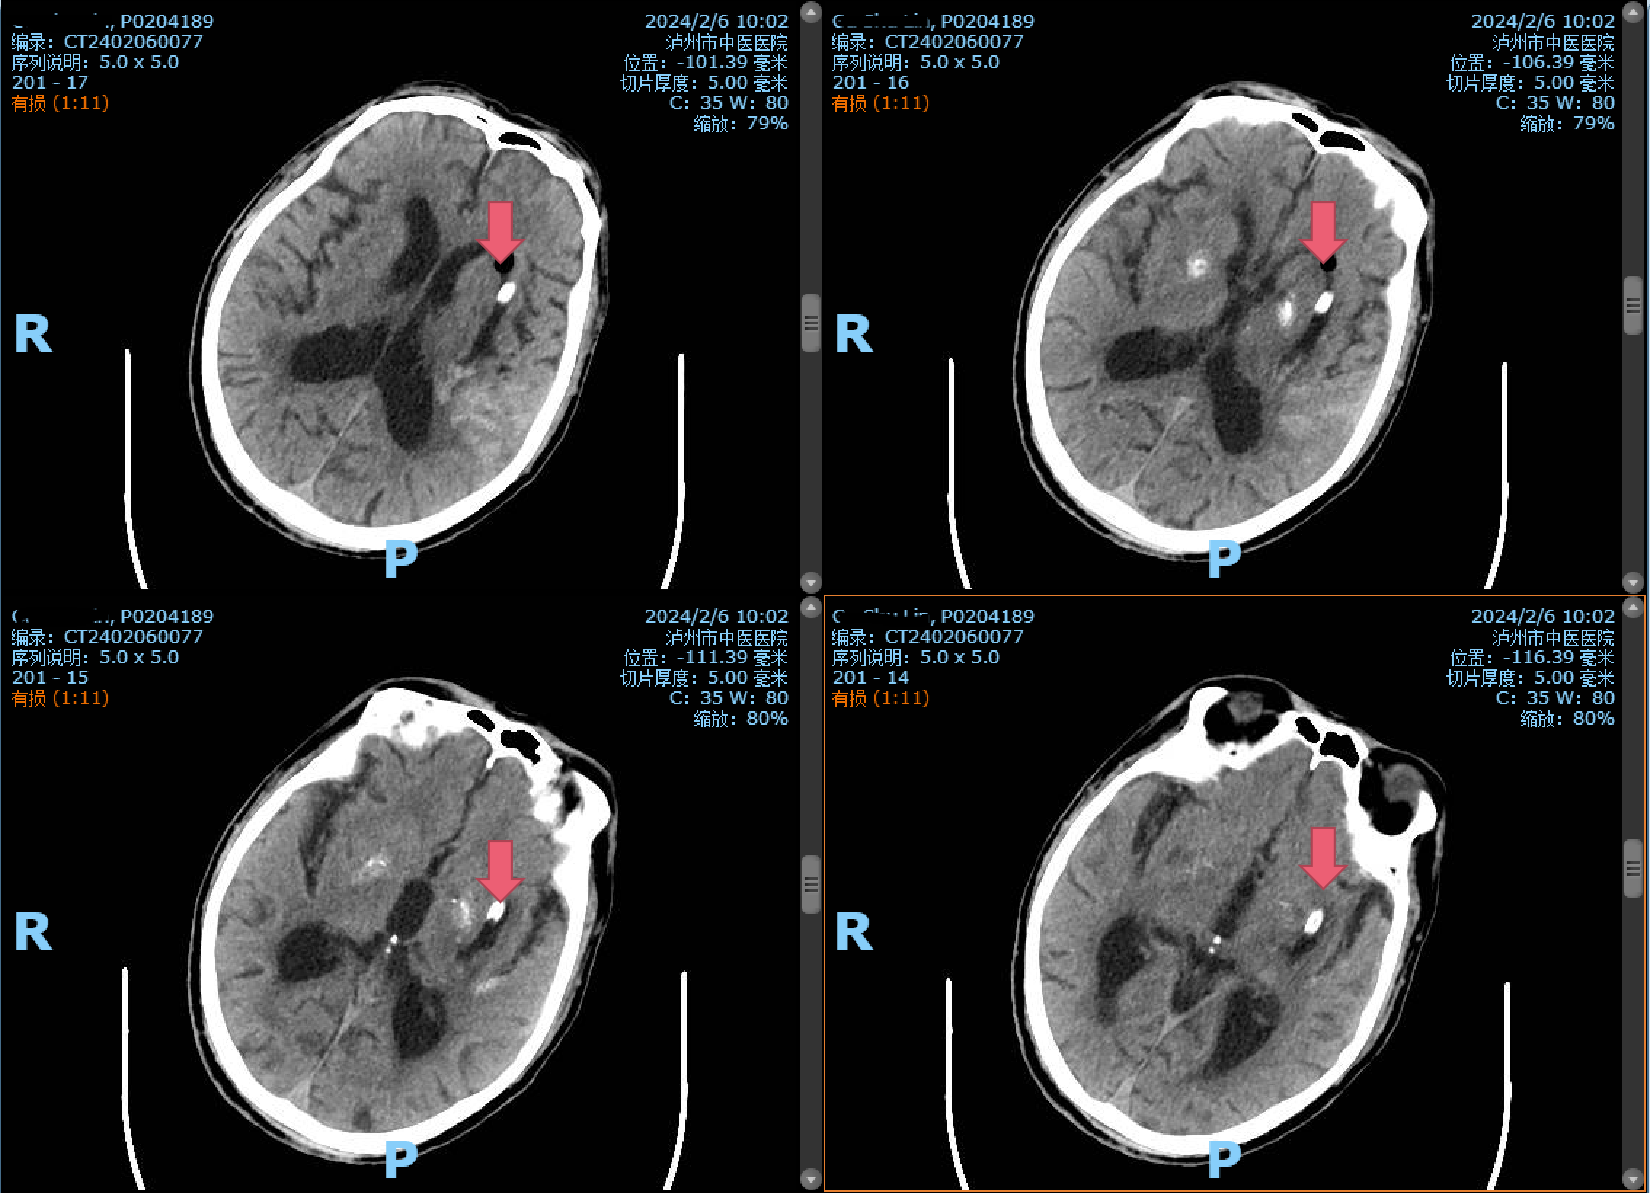

時(shí)間第一,生命至上?;颊呷朐汉笾苯咏?jīng)急救通道,完善頭顱CT,提示腦出血,病情危重,立即及時(shí)、安全地送到了市中醫(yī)院重癥監(jiān)護(hù)室,并通知神經(jīng)外科。入院后由首診醫(yī)師曹飛副主任醫(yī)師接診。經(jīng)過(guò)仔細(xì)詢(xún)問(wèn)病史、查體發(fā)現(xiàn)患者昏迷不醒,呼之不應(yīng)、無(wú)言語(yǔ)。雙瞳形圓不等大,向左凝視,左側(cè)瞳孔直徑約2.5mm,對(duì)光反射消失;右側(cè)瞳孔直徑約3mm,對(duì)光反射消失。右側(cè)肢體肌肉張力高,病理征陽(yáng)性;結(jié)合CT片后診斷為:左側(cè)基底節(jié)區(qū)腦出血伴血腫形成。

術(shù)前CT:左側(cè)基底節(jié)區(qū)腦出血伴血腫形成(紅色箭頭所指)